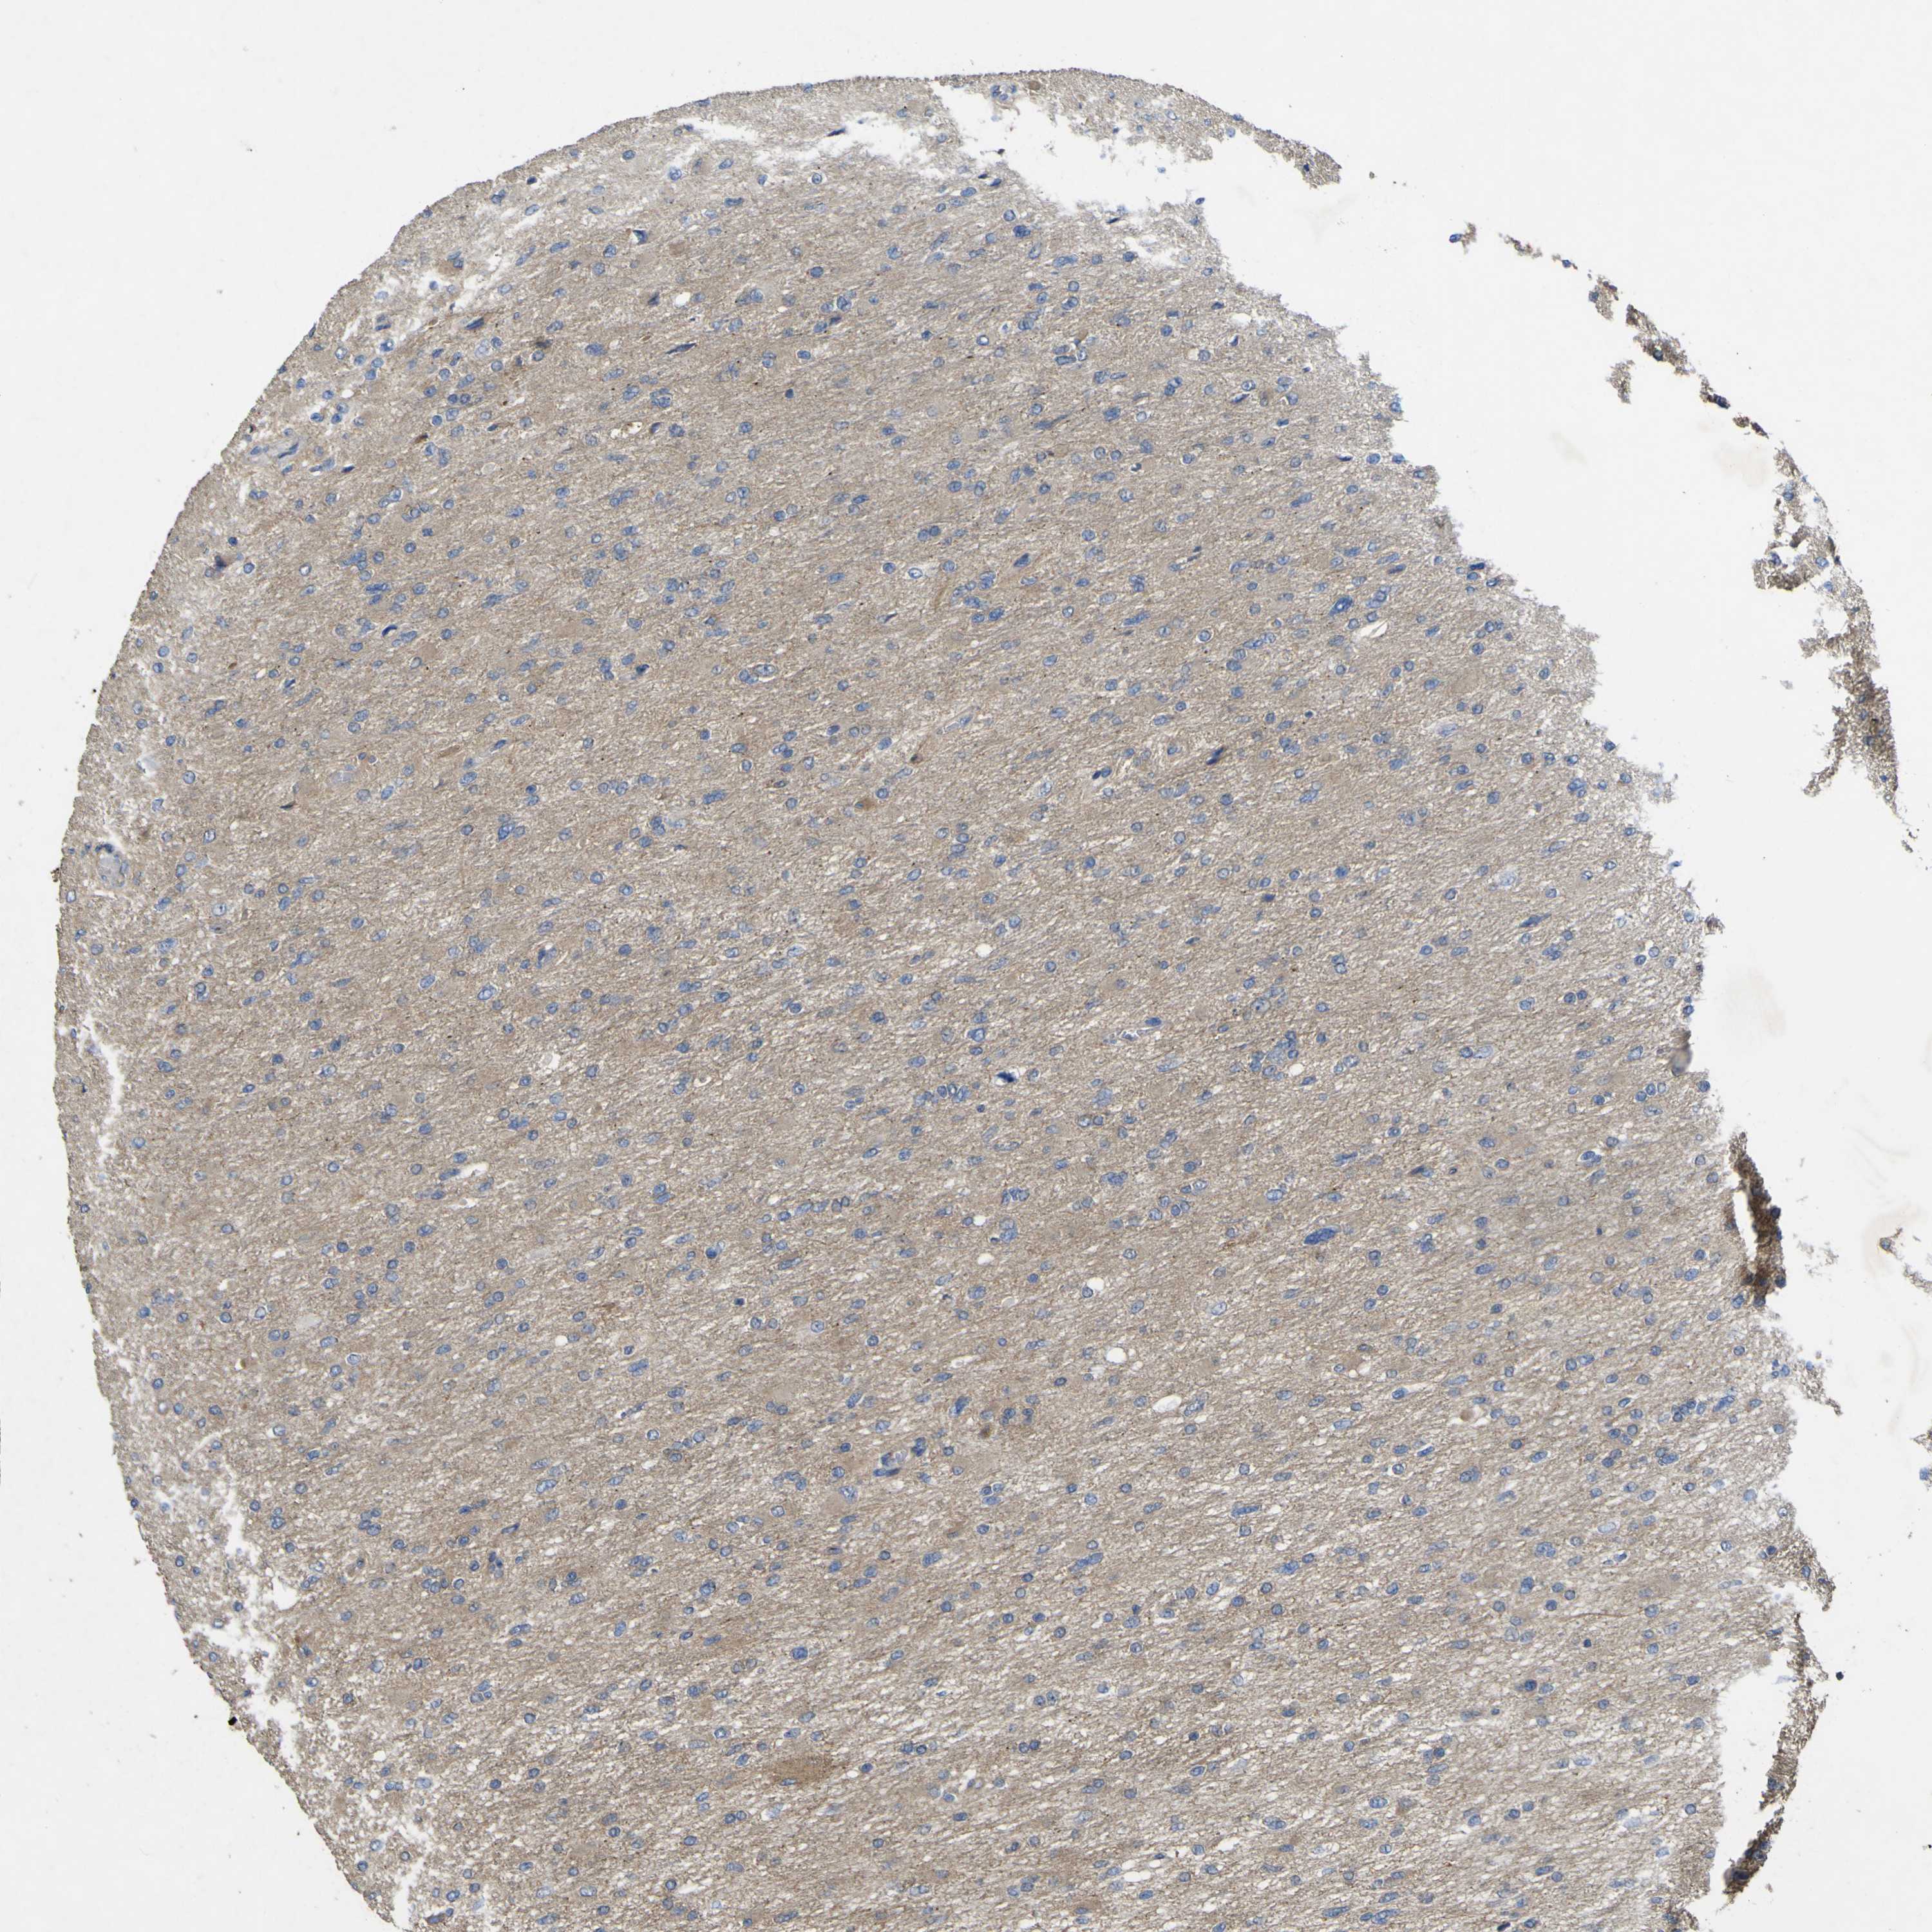

GLIOMA - Protein expressioni

A mouse-over function shows sample information and annotation data. Click on an image to view it in a full screen mode. Samples can be filtered based on level of antibody staining by selecting one or several of the following categories: high, medium, low and not detected. The assay and annotation is described here.

Note that samples used for immunohistochemistry by the Human Protein Atlas do not correspond to samples in the TCGA dataset.

Antibody stainingi

Antibody staining in the annotated cell types in the current human tissue is reported as not detected, low, medium, or high, based on conventional immunohistochemistry profiling in selected tissues. This score is based on the combination of the staining intensity and fraction of stained cells.

Each image is clickable and will lead to virtual microscopy that enables deeper exploration of all samples and also displays staining intensity scores, fraction scores and subcellular localization as well as patient and tissue information for each sample.

Antibody HPA012948

Staining

High

Medium

Low

Not detected

Intensity

Strong

Moderate

Weak

Negative

Quantity

>75%

75%-25%

<25%

None

Location

Nuclear

Cytoplasmic/membranous

Cytoplasmic/membranous,nuclear

Glioma, malignant, High grade

Glioma, malignant, Low grade